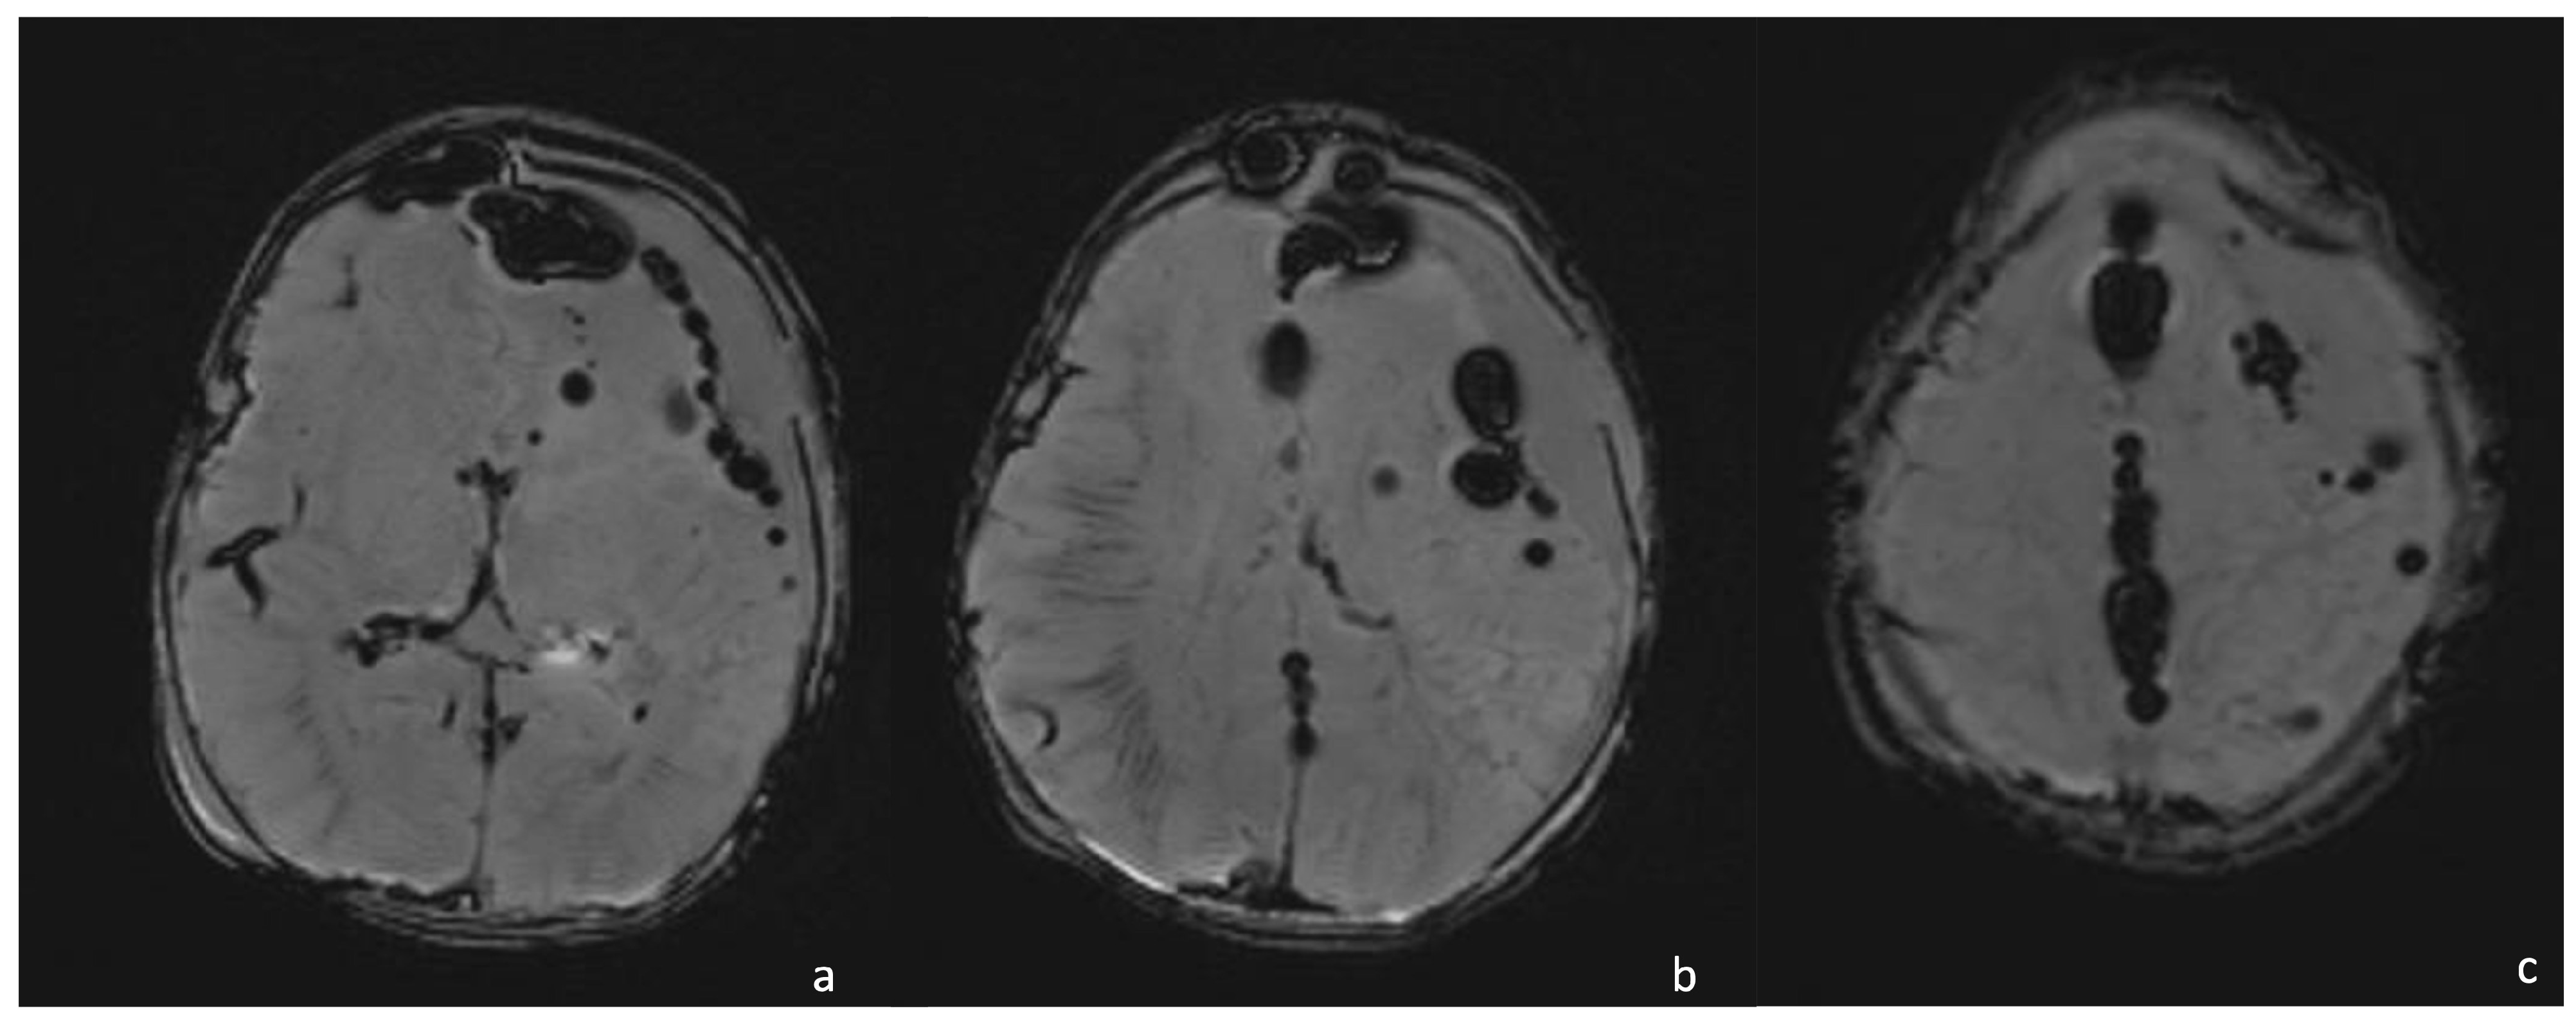

6.1. Cerebritis and Abscesses

- Early cerebritis stage (3–5 days): Bacteria infiltrate the vessels causing vessel wall inflammation and vessel necrosis, which lead to blood barrier disruption and parenchymal invasion. The resulting cerebral infection, namely the early cerebritis, is limited to a focal portion of the brain, does not present a capsule, and presents a coexisting edema. In MRI, early cerebritis is seen as an inhomogeneous and ill-defined area of hyperintensity on T2WI and hypointensity on T1WI, surrounded by edema appearing hypointense on T1WI and hyperintense on T2WI. It presents a diffusion restriction on DWI/ADC in relation to cytotoxic edema and inflammatory hypercellularity. Hemorrhagic foci present as T1WI hyperintense areas within the lesion. After contrast administration, a patchy enhancement is observed, yet no capsule may be identified. On the US, early cerebritis appears as an ill-defined area of inhomogeneous echogenicity presenting increased vascularity on Transcranial Doppler, pairing CT findings, with an ill-defined area of inhomogeneous hypodensity with inhomogeneous and patchy enhancement.

- Late cerebritis (5–14 days): Cerebritis progressively evolves to show a necrotic core and an initial encapsulation. This stage flows into and partly overlaps with the early capsule stage since this last represents a progression with similar, yet more advanced features of the late cerebritis stage. In MRI, the late cerebritis results in a focal formation characterized by a necrotic core, appearing inhomogeneous on both T1 and T2WI, without a complete and regular contrast peripheral enhancement, yet with a defined diffusion restriction on DWI/ADC. On the US, the appearance is similar to the early cerebritis, yet the lesion appears more focal and the core starts becoming hypoechogenic, similar to CT showing a significantly hypodense core in the lesion with irregular and incomplete peripheral enhancement. Early capsule formation (14–30 days): The cerebritis is becoming an abscess since the capsule is evident, yet it is incomplete and thin and appears as a hyperintense rim on T1WI and a hypointense rim on T2WI with contrast enhancement on T1WI.

- Early capsule formation (2 weeks to 2 months): the lesion presents diffusion restriction on DWI/ADC, mainly in relation to hypercellularity. Sonographically, the lesion presents a well-defined hypoechoic core and an incomplete hyperechoic rim. CT shows a well-defined hypodense core and an incomplete peripheral enhancement.

- Late capsule formation (weeks to months): The parenchymal abscess presents a necrotic core, appearing hypointense on T1WI and hyperintense on T2WI with diffusion restriction on DWI/ADC. The capsule is inhomogeneously thick, appearing thicker towards the cortex and thinner towards the ventricles, appears isointense on T1WI and hypointense on T2WI, and presents an intense enhancement. On the US, the abscess presents a well-defined hypoechoic core and a complete hyperechoic rim, pairing CT that shows a well-defined hypodense core and a complete peripheral enhancement.